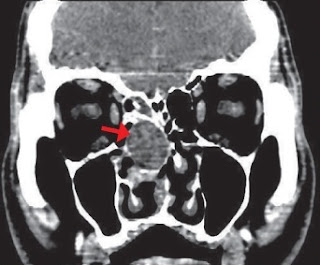

scanner des sinus révèle une volumineuse concha bullosa D dont la cavité

apparaît totalement opaque associée à une déviation septale à convexité G. Les

sinus apparaissent normaux hormis une légère opacité affectant la bulle ethmoïdale

droite.

Scanner des sinus montrant la Concha bullosa D infectée (flèche).

Déviation controlatérale de cloison

Aération normale des sinus de la face.